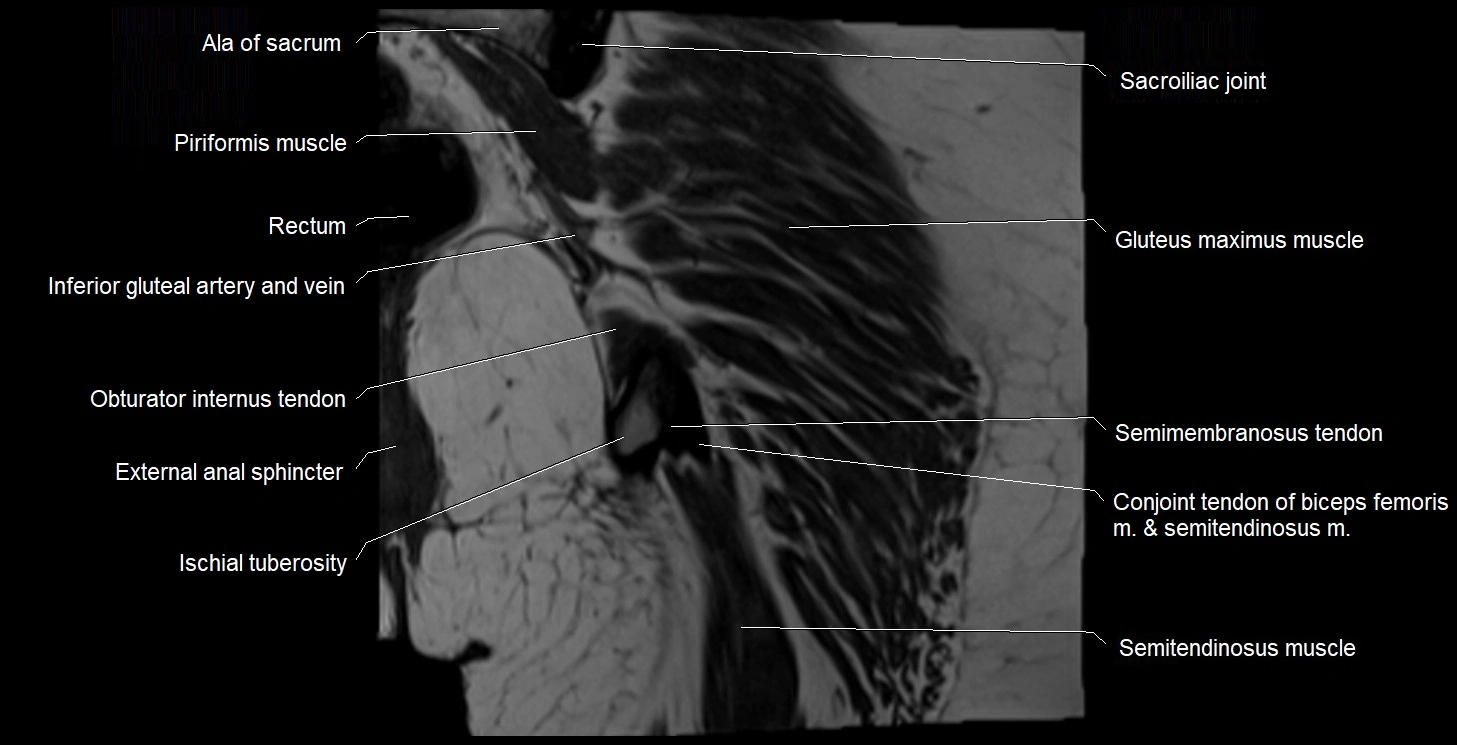

- Ala of sacrum

- Conjoint tendon of biceps femoris & semitendinosus

- External anal sphincter

- Gluteus maximus muscle

- Inferior gluteal artery

- Inferior gluteal vein

- Ischial tuberosity

- Obturator internus tendon

- Rectum

- Sacroiliac joint

- Semimembranosus tendon (proximal)